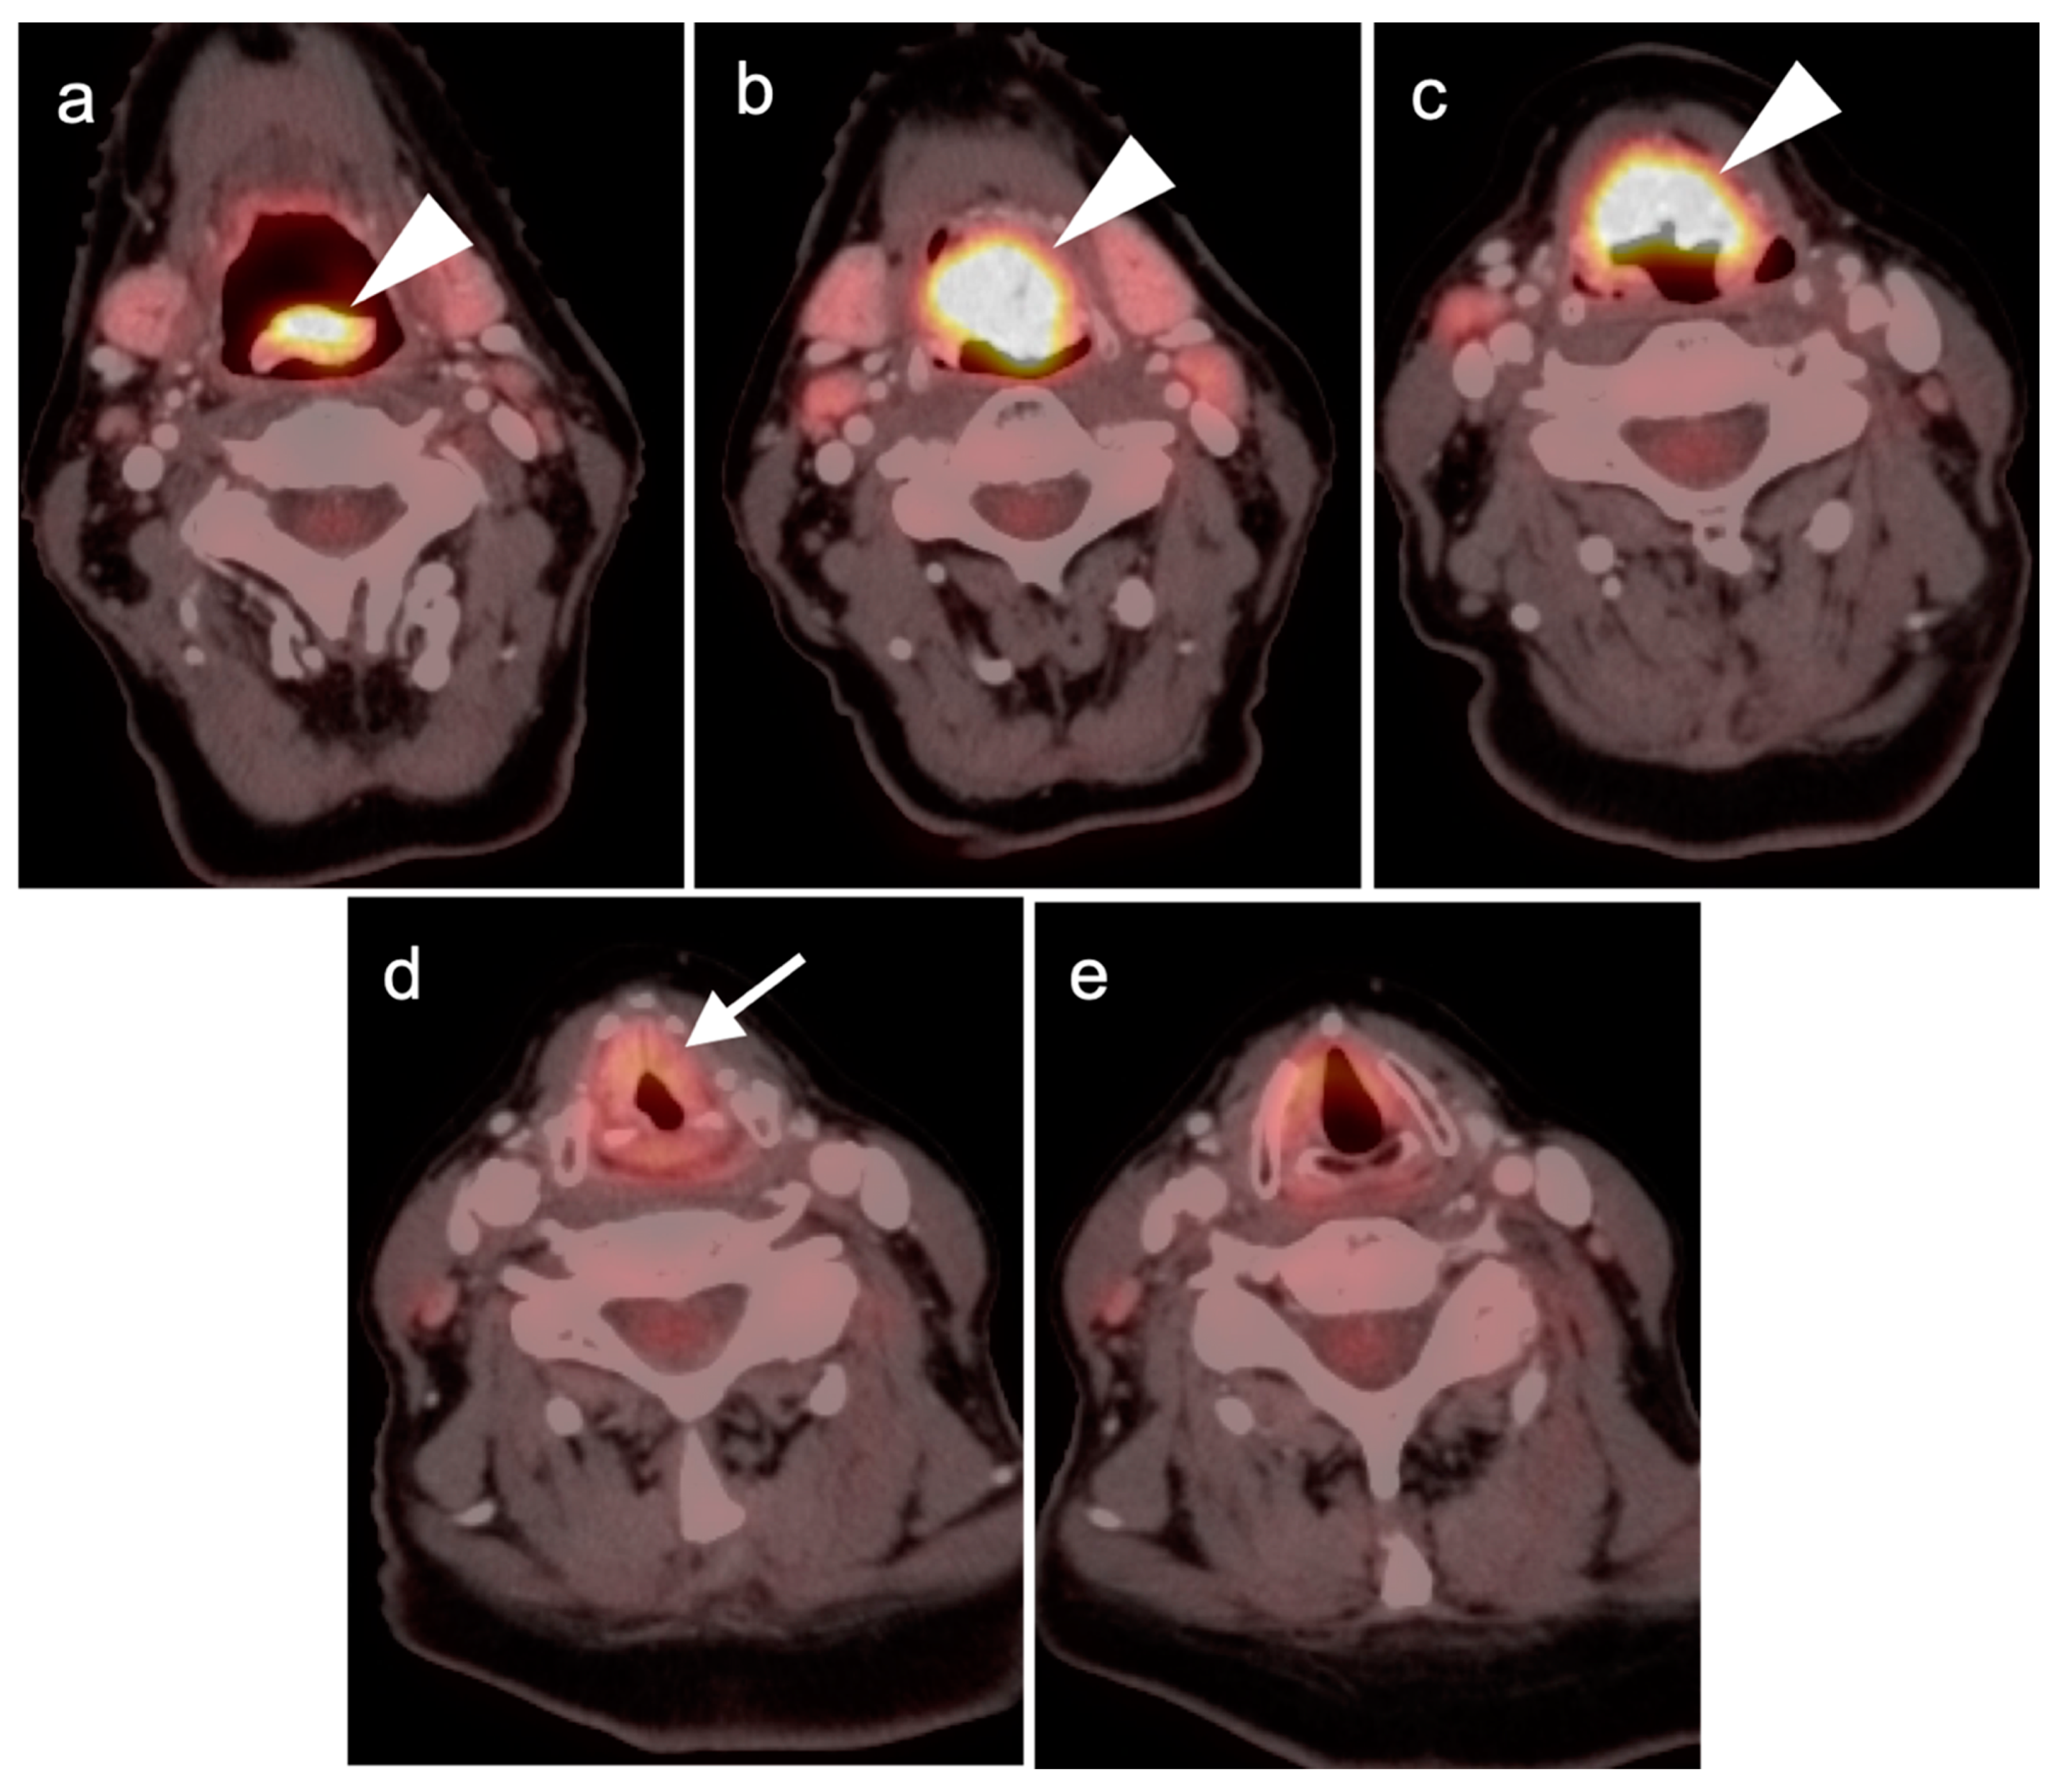

2.2. Squamous Cell Carcinoma of the Head and Neck (SCCHN)

2.6. Thyroid Cancer

- Anaplastic thyroid cancer